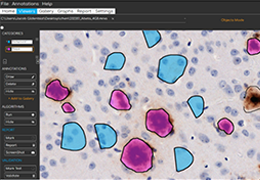

分析智能。

这些功能利用数字控制面板分析运营、业务和临床绩效。

使管理员能够跟踪关键参数,包括平均曝光率、拒绝的影像和探测器统计信息。

帮助确定需要改进的方面,支持为员工和部门制定适当的改进计划。